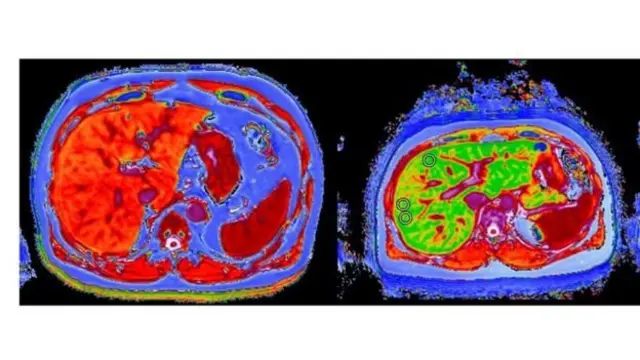

یک نوع تصویربرداری ام آر ای جدید نشان داده که کبد او سالم شده است.

این ام آر آی جدید که دانشگاه آکسفورد ساخته شده در کنفرانس جهانی کبد در پاریس برای اولین بار معرفی شد. در این روش به کمک یک نوع نرم افزار به نام "لیورمولتیاسکن" (LiverMultiScan) ماهیت بیماری کبد و شدت آن را اندازهگیری میکنند.

منبع تصویر، PERSPECTUM DIAGNOSTICS

"این اسکن کل کبد را نشان میدهد در حالیکه نمونه برداری با سوزن فقط از یک بخش کوچک انجام میشود و کمی ناراحت کننده است. علاوه بر این در این نوع ام آر ای بیماران پس از مدتی میتوانند دوباره اسکن کنند تا از بهبود کبد مطمئن شوند."